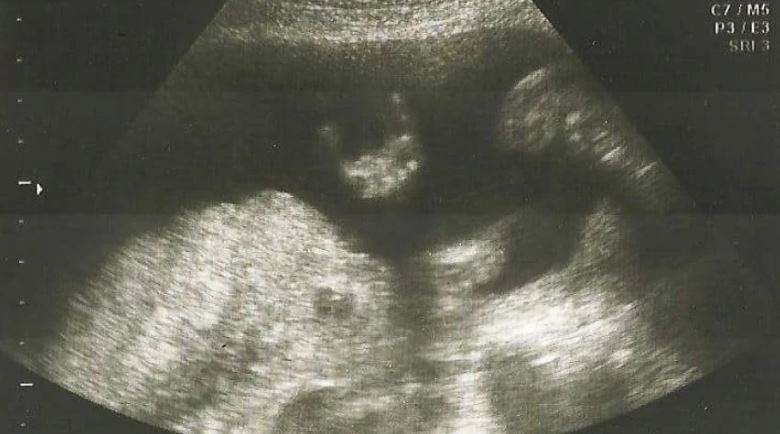

De terror

Como le pasó a Carrington, una madre australiana se llevó una desagradable sorpresa al ver por primera vez imágenes de su bebé, en la panza.

Sharni Turner, la embarazada, quedó muda al darse cuenta que su bebé tenía un aspecto terrorífico. La inusual ecografía refleja la toma frontal de la cabeza del feto, pero en lugar de una silueta armónica, parece la cara de un monstruo.

Para nosotros parece un "Depredador", el extraterrestre que en las últimas películas peleó con los "Aliens".